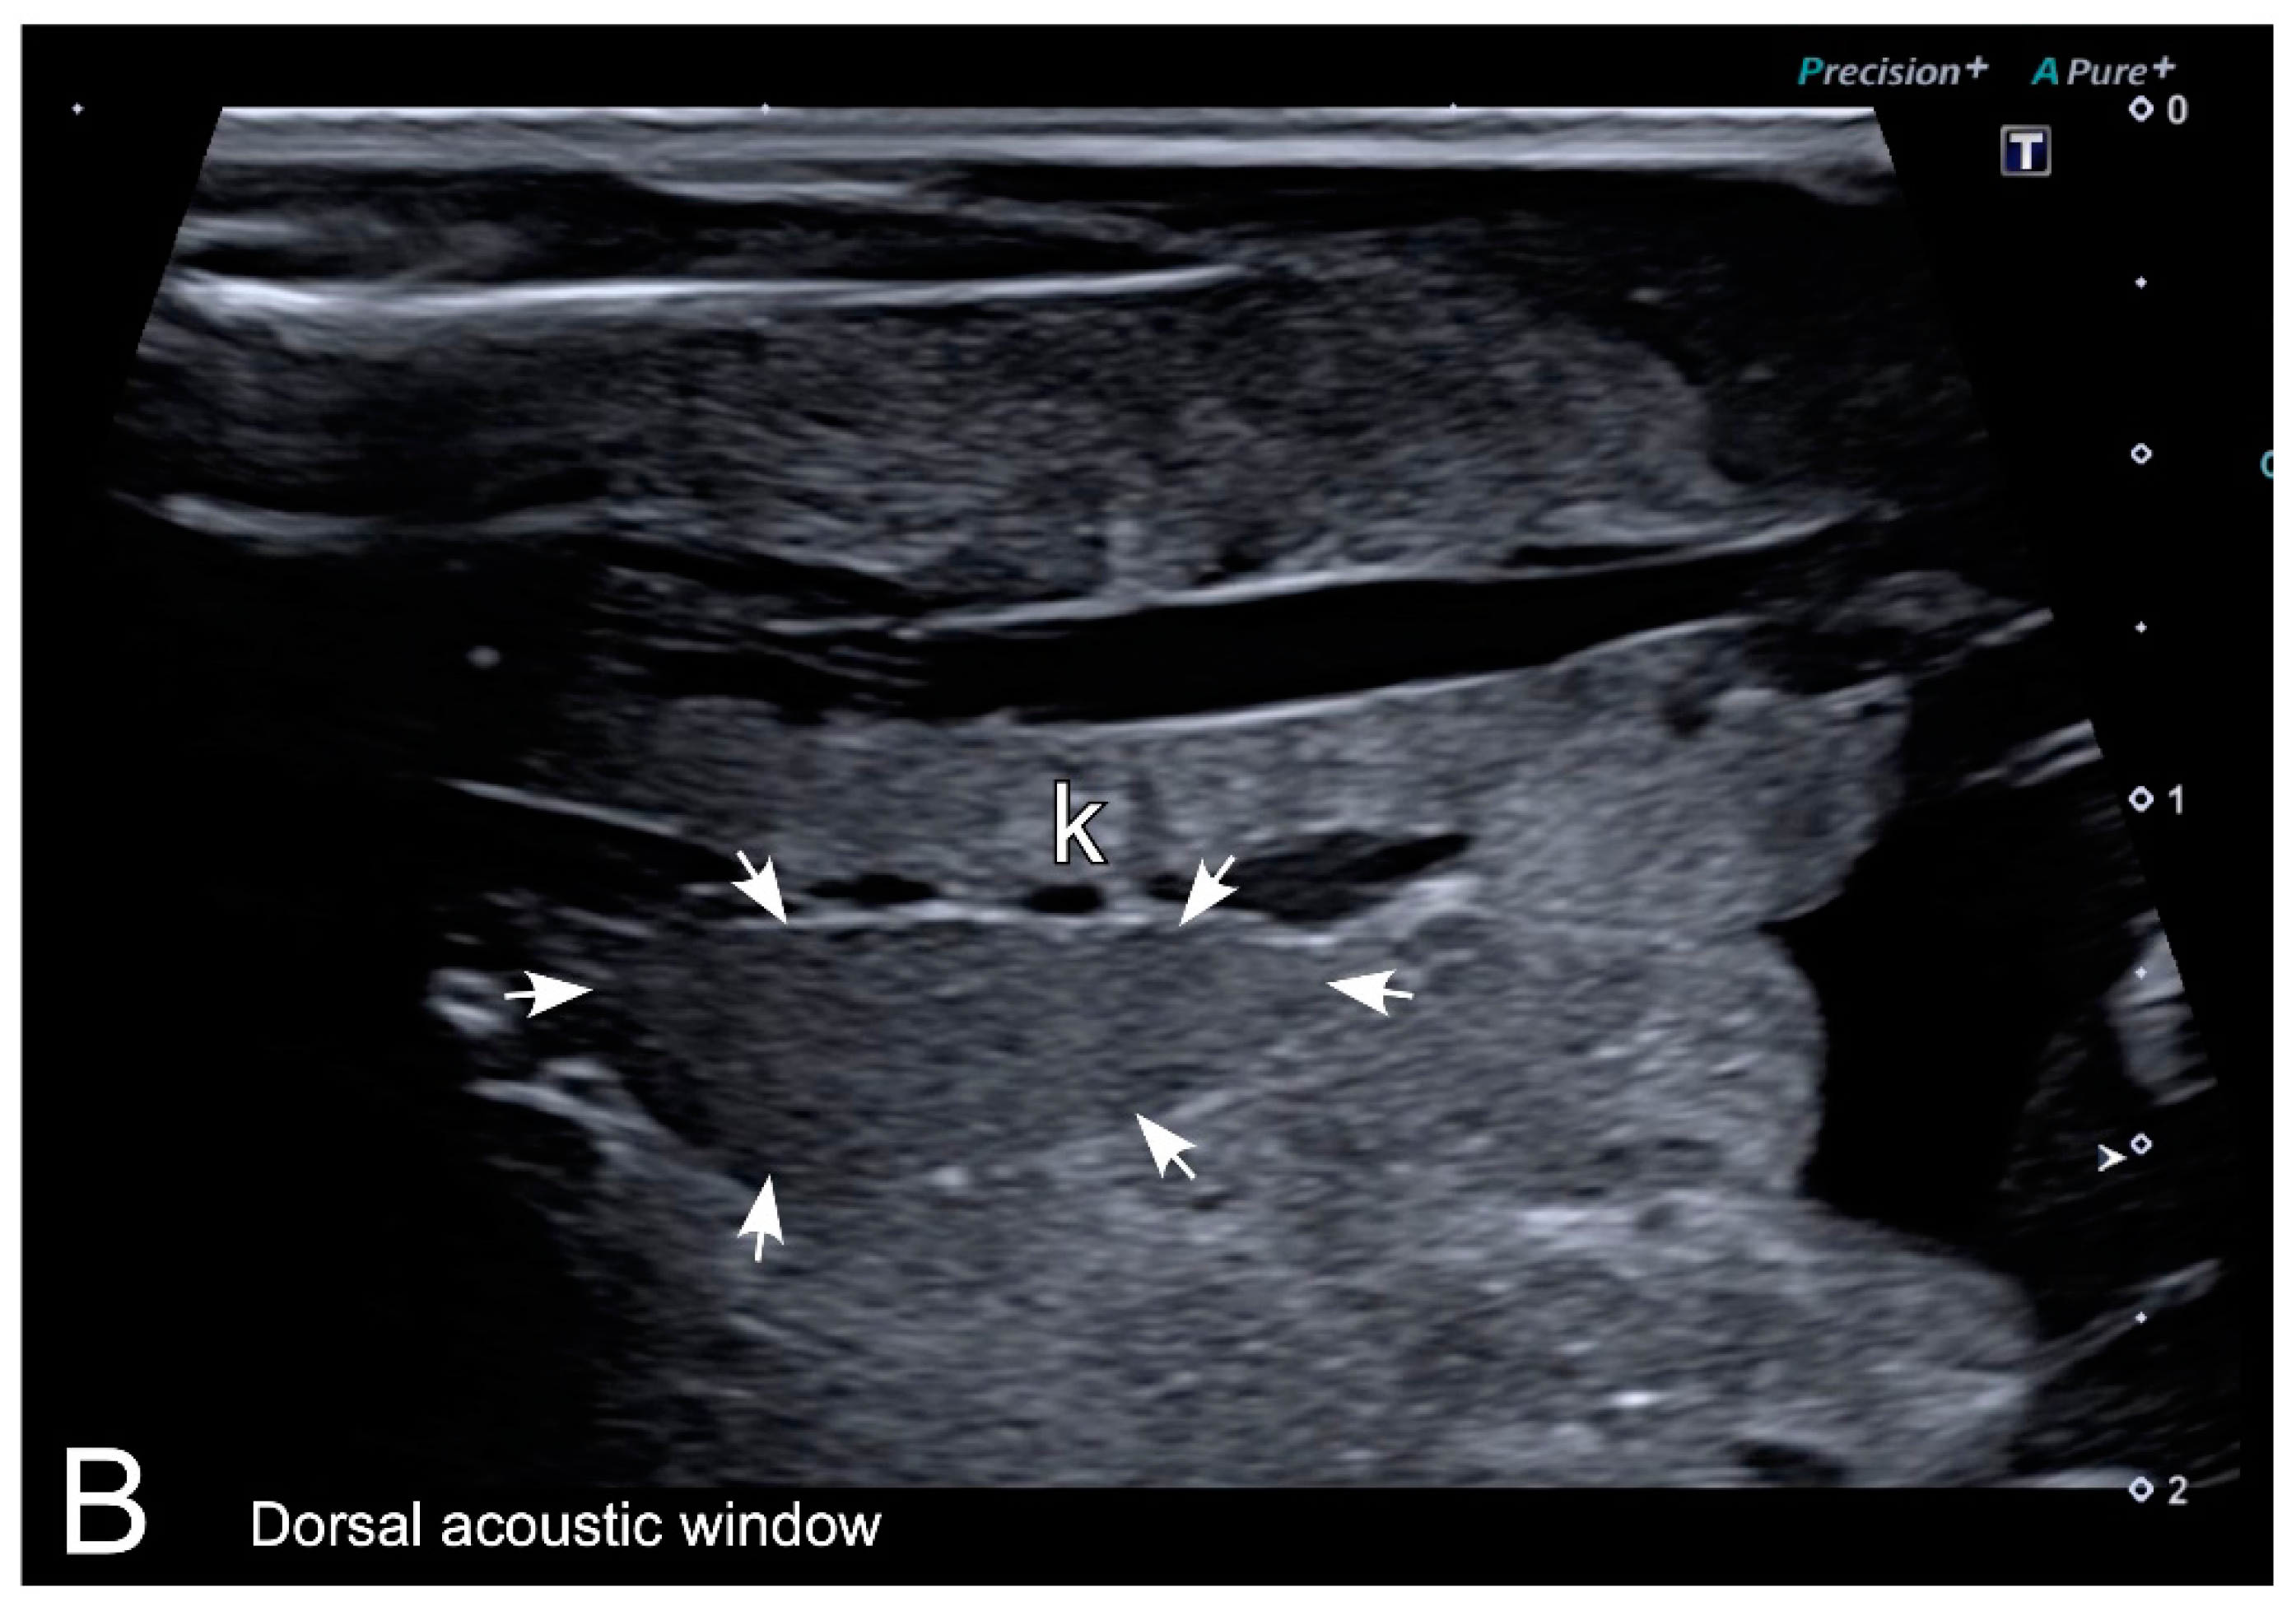

3.2. Ultrasonography